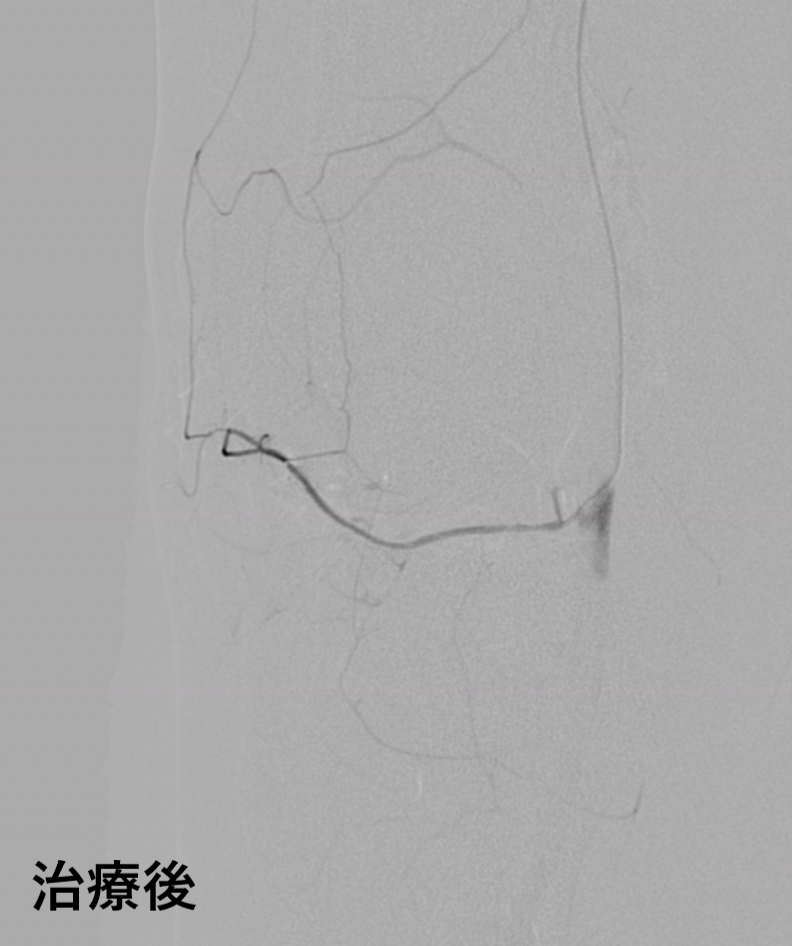

医療法人社祐優会オクノクリニック総院長の奥野祐次は、第49回日本肩関節学会において、SIRVA(シルバ)の国内での発生状況や、疾患の特徴、およびSIRVAに対する新しい治療を開発しその有効性を発表しました。SIRVA(シルバ)は医療従事者でもまだ知らない方も多く、一般の人ではSIRVA(シルバ)を知らずワクチン接種後の痛みに困っている方もかなり多いと想定されます。今後も私たち痛みの専門オクノクリニックとしては啓発活動を行い、この病気の認知を広め、多くの人が路頭に迷わないように努めていきたいと思います。